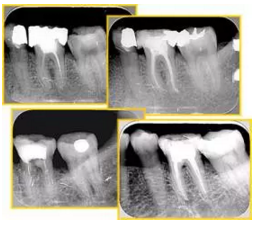

6. 術(shù)后 X 線片

術(shù)后 X 線片用來評定根管充填 長度、致密度(管壁清晰、側(cè)枝)等指標(biāo)。

圖為根管充填術(shù)后 X 線片。圖中可見,根管充填較好。右下圖有白色小點,為側(cè)方加壓導(dǎo)致糊劑擠出所致,表明根管充填比較致密。

致密、恰到好處的充填可去除干凈根管里感染灶,機(jī)體逐漸恢復(fù)。

多根牙時候需進(jìn)行偏移投照,正位投照無法說明具體哪根牙根管充填效果。